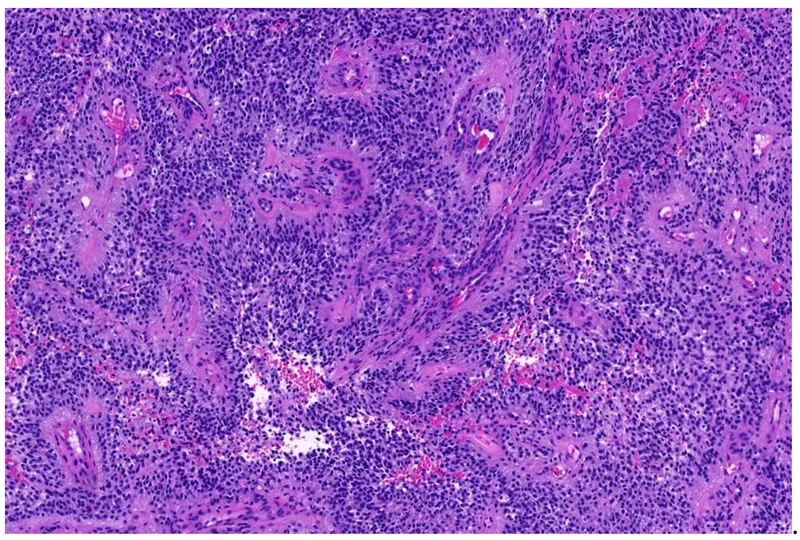

- Histology: Invasive cords/nests of atypical squamous cells with eosinophilic cytoplasm, large pleomorphic nuclei, and characteristic keratin pearls.

- Squamous Cell Carcinoma (SCC) is linked to UV exposure and immunosuppression; histology reveals characteristic keratin pearls.